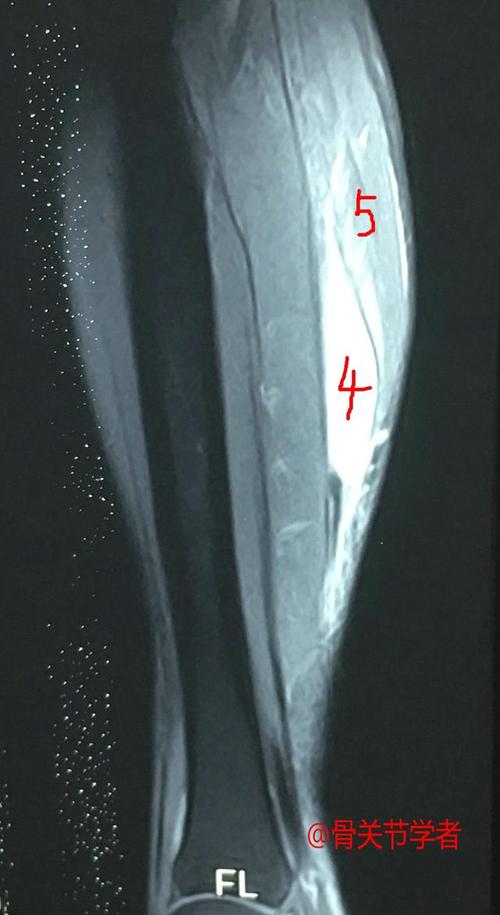

第二天患者查的磁共振结果也出来了,患者内侧腓肠肌撕裂,腓肠肌内侧